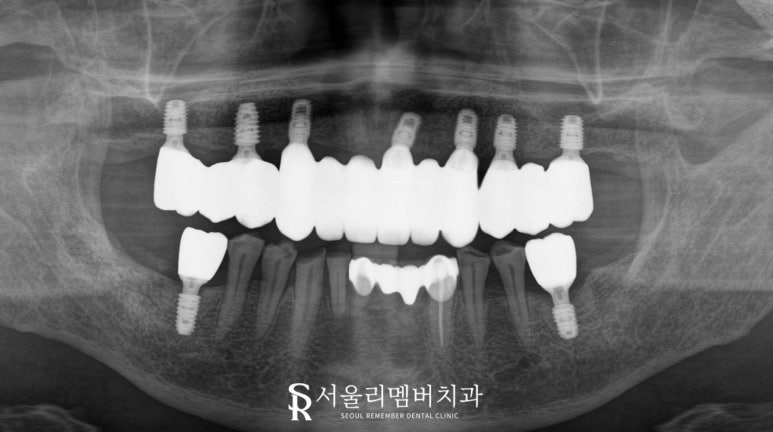

2024.07.01

보철물은 브릿지 형태로 설계되었는데,

이는 개별로 존재하는 싱글 크라운보다

비용 효율적이면서도 높은 강도를 제공합니다.

픽스처를 심지 않은 부위에는

인공치(pontic)를 올려

치아머리 기능을 할 수 있도록 해주는 것이죠.

또한 서울대입구역 치과 에서는

상악 전체 임플란트 브릿지의 경우,

교합 조정이 매우 중요하게 여기는데요,

교합이란 위아래 치아가 맞물리는 방식을 의미하며,

부적절한 교합은 많은 문제를 일으킬 수 있습니다.

과도한 측방력 발생으로 인한 수술 실패

보철물의 파절 또는 탈락

턱관절 장애

두통 및 안면 통증

그래서 서울대입구역 치과 에서는

개인마다 다른 구강 상태를 파악하고

완성된 보철을 세심하게 조정하여

저작 시 모든 부위에 힘이 균등하게 분산될 수 있게

여러 차례 체크하는 과정을 거칩니다.

2024.02.27 ~ 2024.07.01

모든 진료가 끝난 후

자연치와 거의 유사한 저작력을 회복할 수 있으며

발음과 심미성도 크게 향상되었습니다.

무엇보다 틀니의 불안정성에서 벗어났다는 점이

제일 큰 변화가 아닐까 싶습니다.